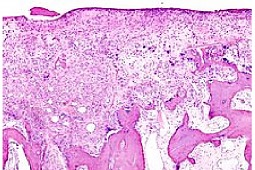

Reumatoidalne zapalenie stawów